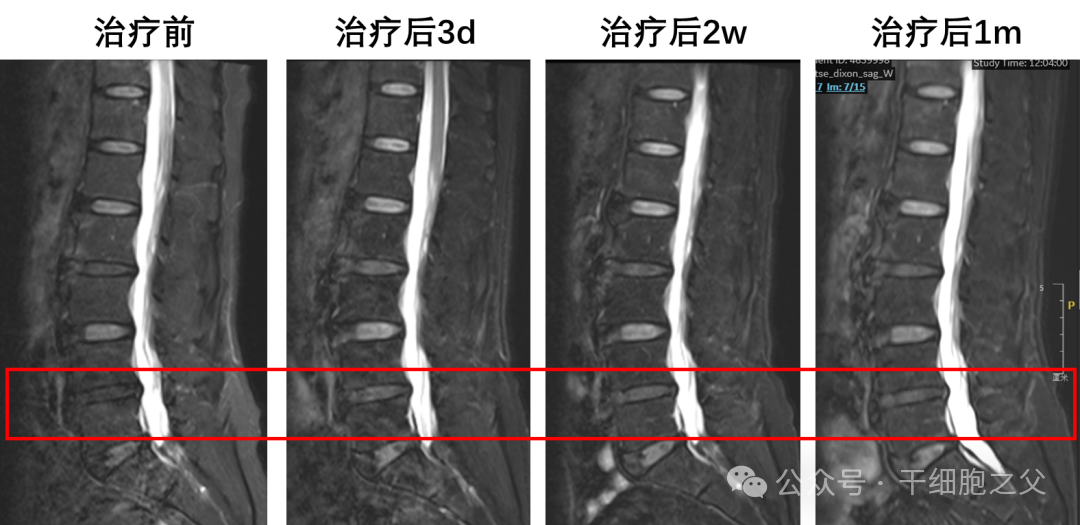

首剂量组的全部受试者在接受“FibroCell-001注射液”治疗之后,情况平稳,各项指标正常,无手术及围术期的并发症,均于术后2日顺利出院并继续康复锻炼。随访数据表明,受试者的腰痛和腰椎失稳有显著改善,退变椎间盘的信号强度明显恢复。